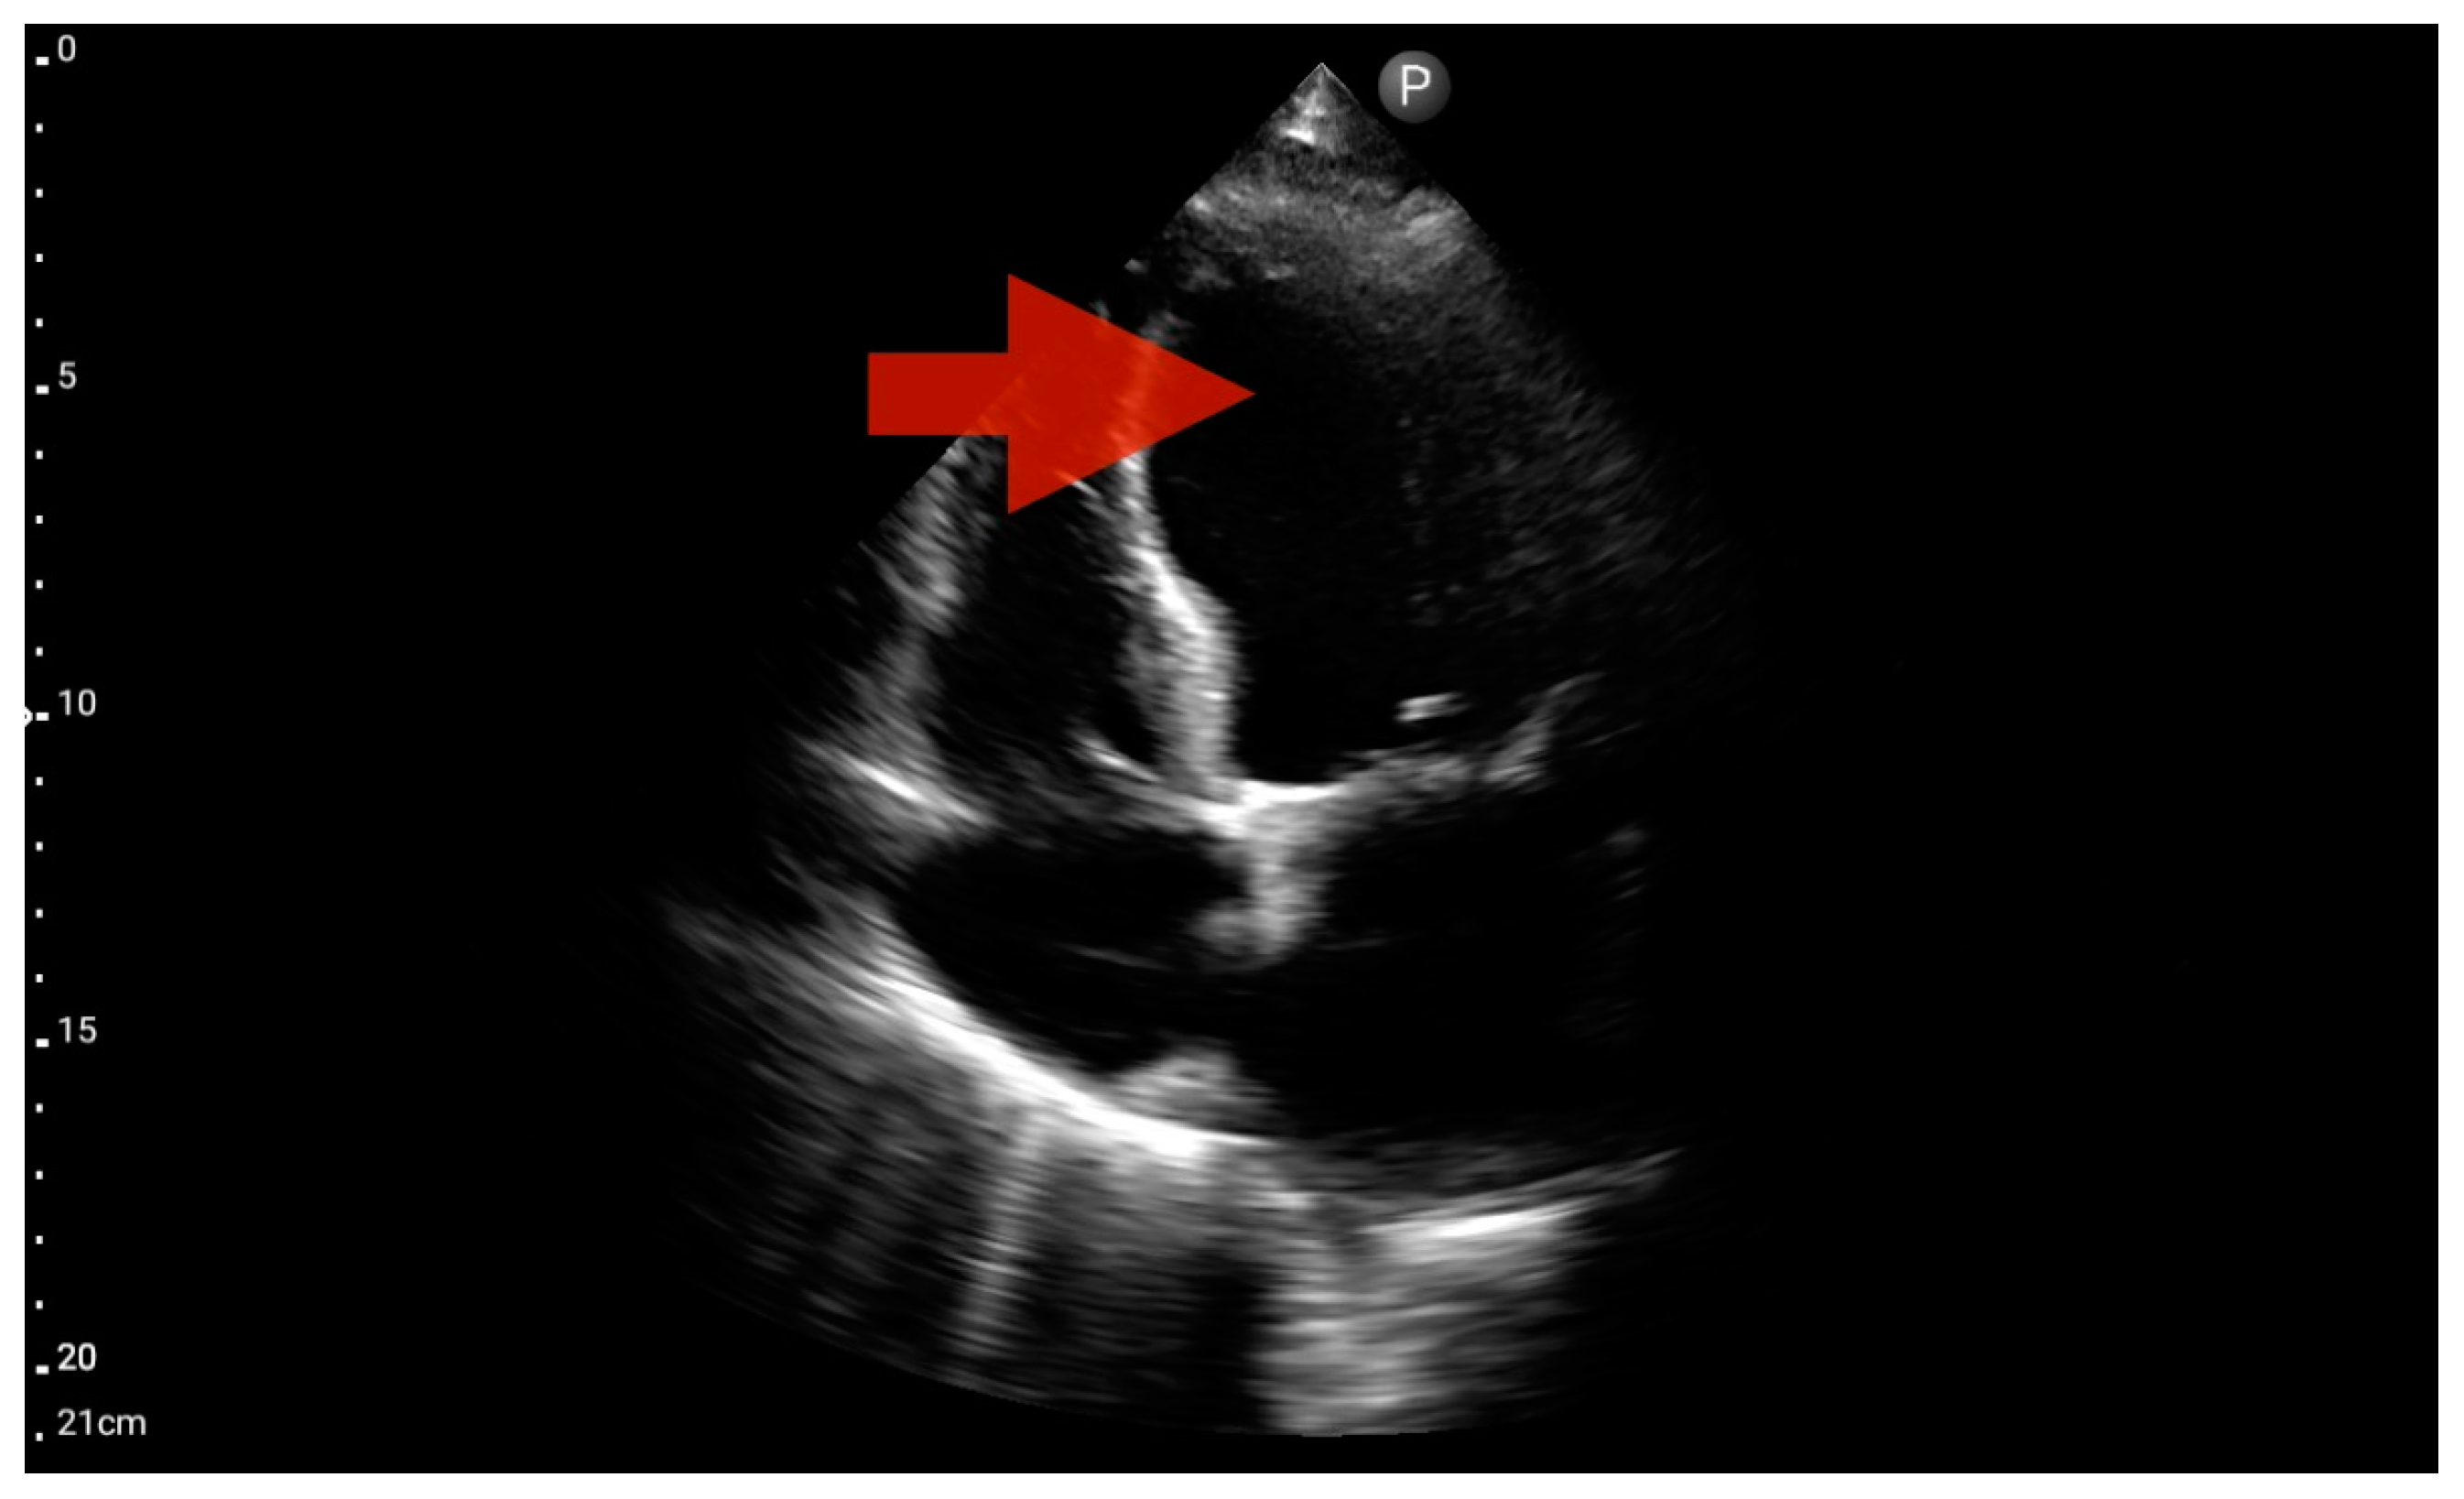

Other detected pathologies, including left ventricle enlargement (2 patients; 12.5%) (Figure 12), right ventricle enlargement (2 patients; 12.5%) (Figure 13) and pericardial effusion (1 patient; 6.25%) (Figure 14), were observed only incidentally. Therefore, further validation in a larger-scale study is warranted to analyze the significance of these symptoms in the pre-hospital setting.

Figure 13.

Right ventricle enlargement; position: parasternal long axis (FATE protocol). Sector probe; the right ventricle is marked with the red arrow, and a significant enlargement of the right ventricle is visible, with a shift of the interventricular septum towards the left ventricle, and an ultrasound picture suggesting pulmonary embolism (source: author’s material—DK).